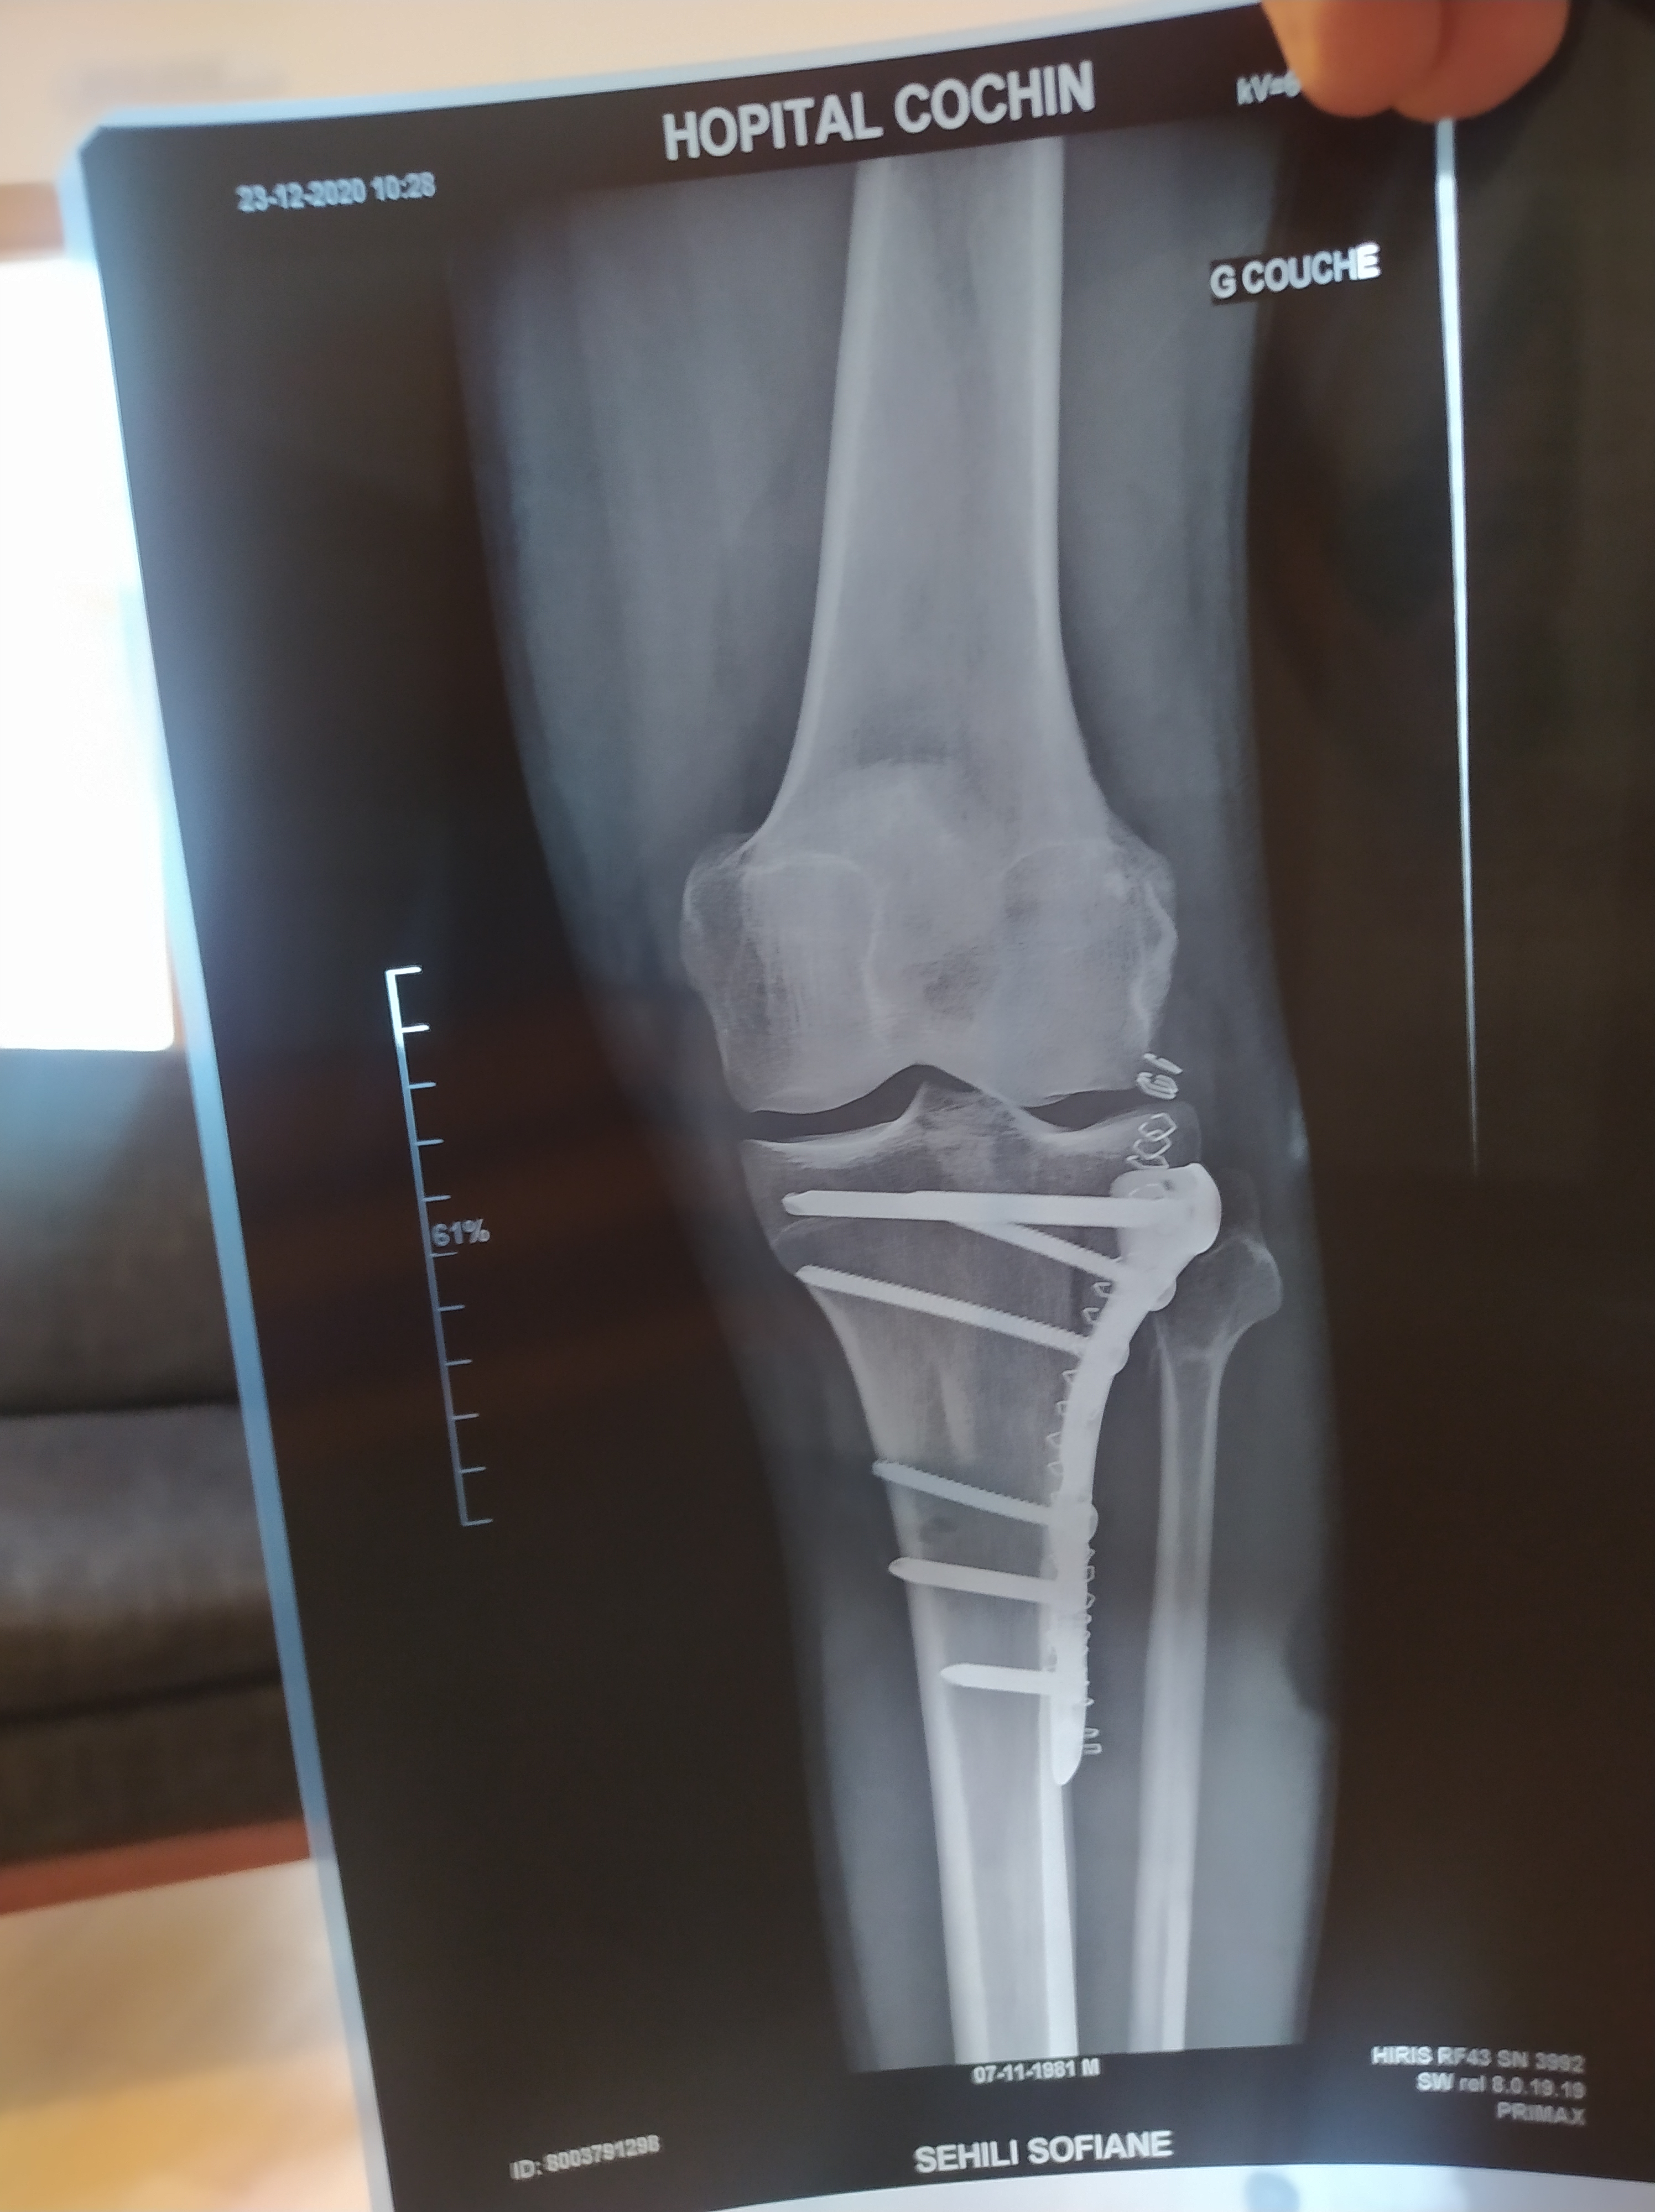

December 4th 2020, mid-day. I’m on my way to make the last delivery of my shift. I’m riding fast on a wide boulevard when suddenly a truck stops right in front of me. I brake but can’t avoid it. My knee hits the backdoor flush and I fall to the ground, screaming in pain like never before. I can’t get up… An ambulance picks me up and drops me off at the nearest hospital. A couple of hours later, a doctor comes to see me with the x-ray and some bad news: the upper part of my tibia is separated in two fragments. I’m not going to be able to ride a bike for 3 months. I feel like the world is crumbling around me. It seems unreal. It can’t happen. Not to me at least. Sure it happens every day, but not to me. That’s not possible.

In the meantime, I was struggling with sadness and a form of anxiety. A lot of negative and dark thoughts, about death and decay. For example, I thought of the plate of titanium the surgeon screwed to my tibia and the fact that it would outlive the bone. I imagined the piece of metal intact in my coffin when my body would be long gone. Having something unalterable inside my body reminded me of my own mortality. This body that seemed capable of extraordinary feats now appeared so fragile.